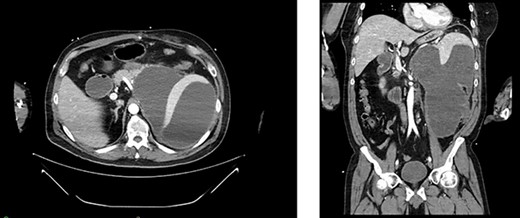

Serial CT scans at 10 and 12 weeks post-resection revealed reduction of the retroperitoneal abscess and appearance of liver lesions concerning for metastasis (Fig. 4). The patient eventually completed his radiation course with no additional problems.

First appearance of multiple liver lesions suspicious for metastasis in transverse (left) and coronal (right) planes on CT; reduction of retroperitoneal effusion can also be seen.